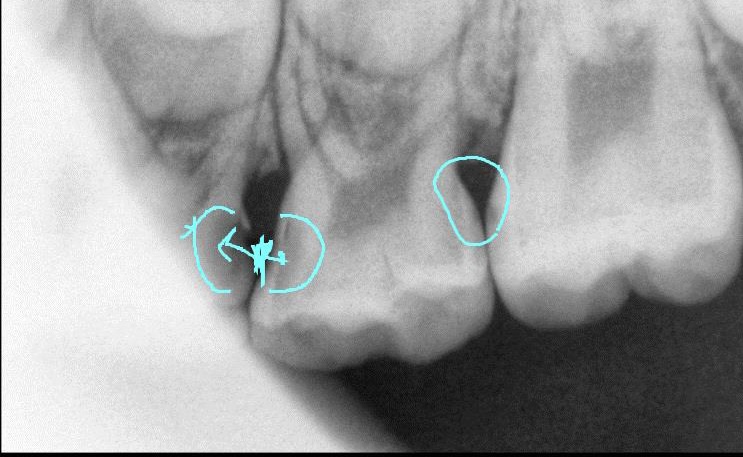

육안으로 보이지도 않고 아프지도 않은 충치들 모두 제거 하는게 맞을까요?(육안으로 보이고, 과거 한참 아프다고 했고 현재는 안아프다고 하지만, 검은 구멍이 생기고 음식이 많이 끼는 불편한 곳은 왼쪽 윗니 뒤에서 두번째 사이입니다)

제일 불편한 왼쪽 윗니